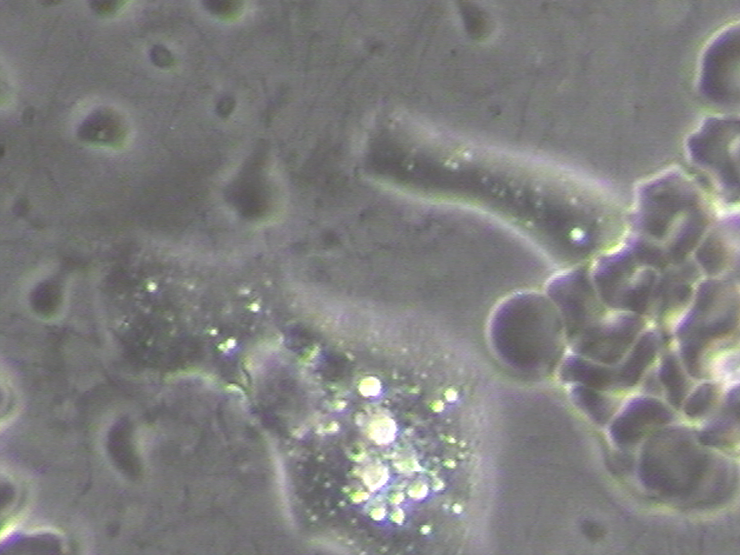

In order for the red blood cells to remove acidic metabolic waste and to pick up life giving oxygen they must pass through the pulmonary vein and then into the capillary pools. If the red blood cells are in pathological coagulation or aggregation there is no way to enter. Why? Because the entry into the capillary venules that branch off from the pulmonary vein measure 3 to 5 microns (1 micron is 1/25,000 of an inch – See Micrograph 1) and a single red blood cell measures 7 microns which makes it impossible for the red blood cell to enter the capillary venules if they are aggregated or coagulated into groups of red blood cells! [4]

When red blood cells group or clot together into a fibrin net, a clotting protein created when there is injury to the cell membrane and/or endothelial cells that protect the lining of blood vessels, (See Picture 2) the red blood cells cannot enter into the pulmonary vein and then into the capillary pools to release their acidic carbon dioxide waste and pick up oxygen in the alveolus of the lungs. (See Illustration 1)[5]

Pathological blood coagulation or disseminated intravascular blood coagulation (DIC) inside the pulmonary vein will prevent the free passage of red blood cells into the alveoli of the lungs via the pulmonary capillaries. {See Phase Contrast Micrograph 3 and 4) Erythrocytes or red blood cells must go into the pulmonary capillaries single file. If they cannot pass into the pulmonary capillaries of the lung to the alveoli this will cause oxygen deprivation that leads to red blood cell hypoxia (carbon dioxide poisoning) degeneration, genetic mutation, sepsis and sudden death.[6][7][8]

Live and Dried Blood smears are both non-invasive blood tests that were used in viewing anatomically the conditions of the red and white blood cells in Disseminated Intravascular Coagulation (DIC), Thrombosis, Rouleau, the ‘Corona Effect’ and Acanthocytosis. (See Phase Contrast Micrograph 7)[12]